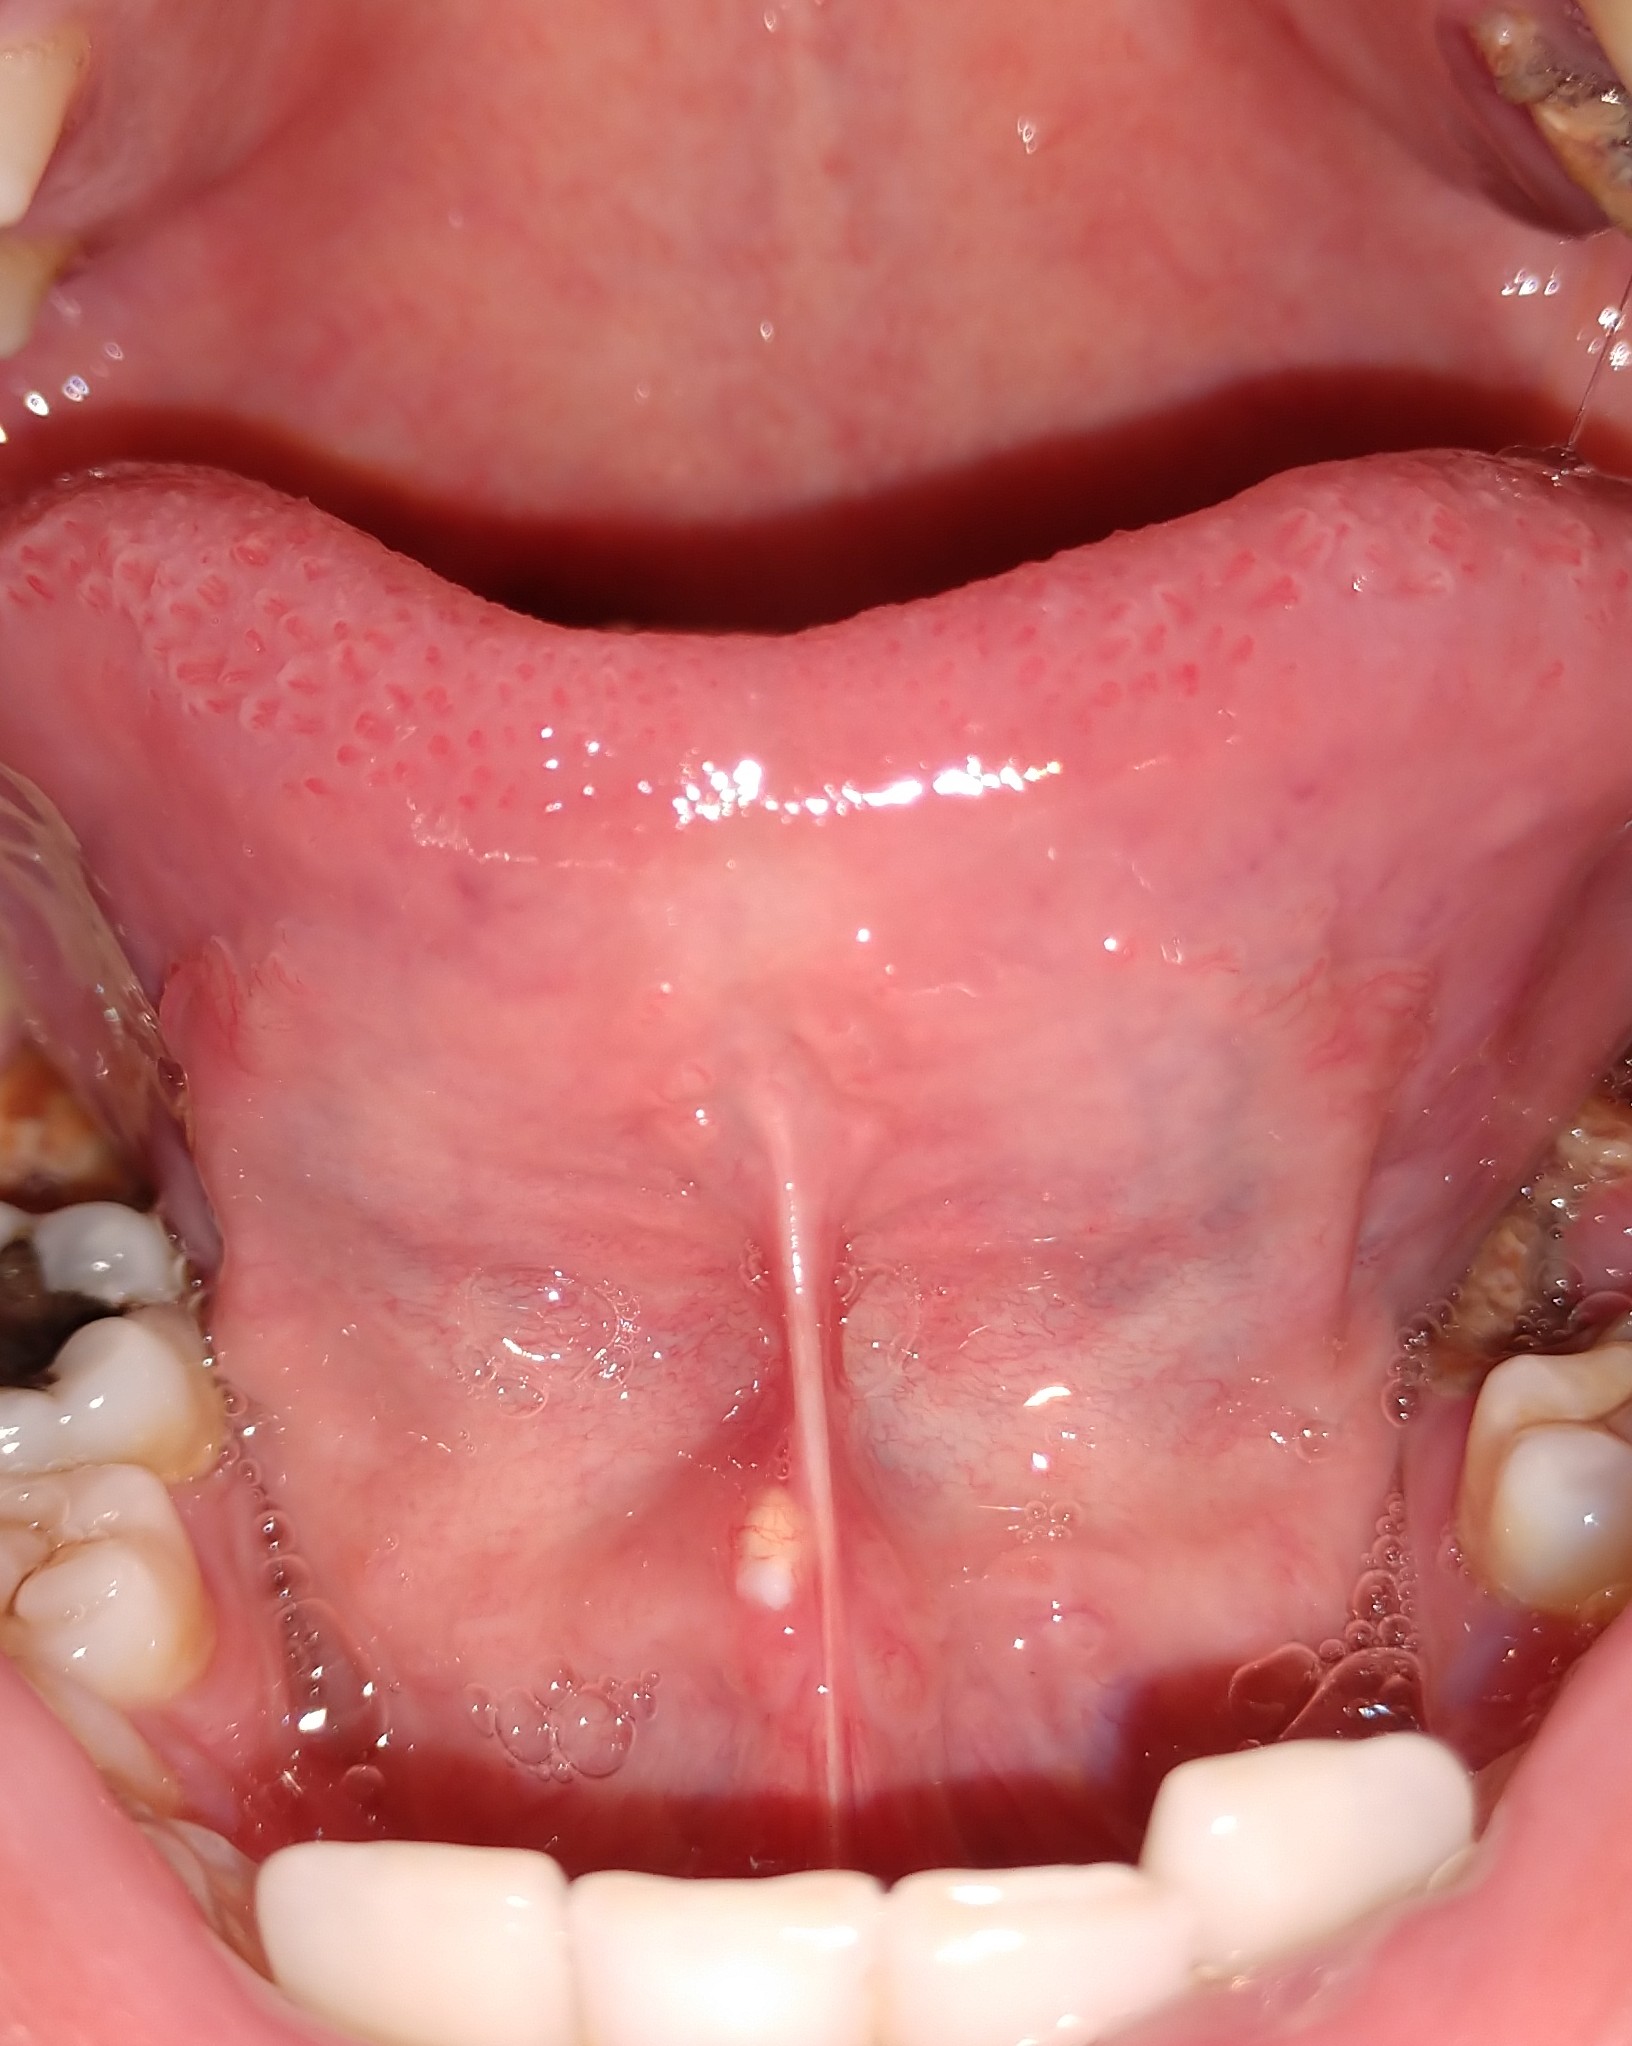

มีติ่งโผล่ออกมาไต้ลิ้นเป็นเพราะอะไรครับ

สวัสดีครับ ขออภัยที่รูปมันไม่สุภาพนะครับ มีไครเคยเป็นแบบนี้มั้งมั้ยครับสังเกตุเห็นมา2วันแล้ว

มันเกิดจากสาเหตุอะไรครับ ตอนนี้รู้สึกกังวลมากแต่ว่ายังไม่มีเวลาไปหาหมอ *ขอบคุณสำหรับคำตอบครับ